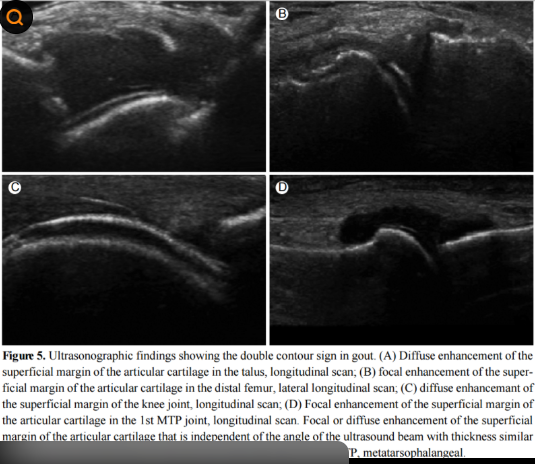

③ 영상 검사

- 초음파: 초기 통풍 확인 가능